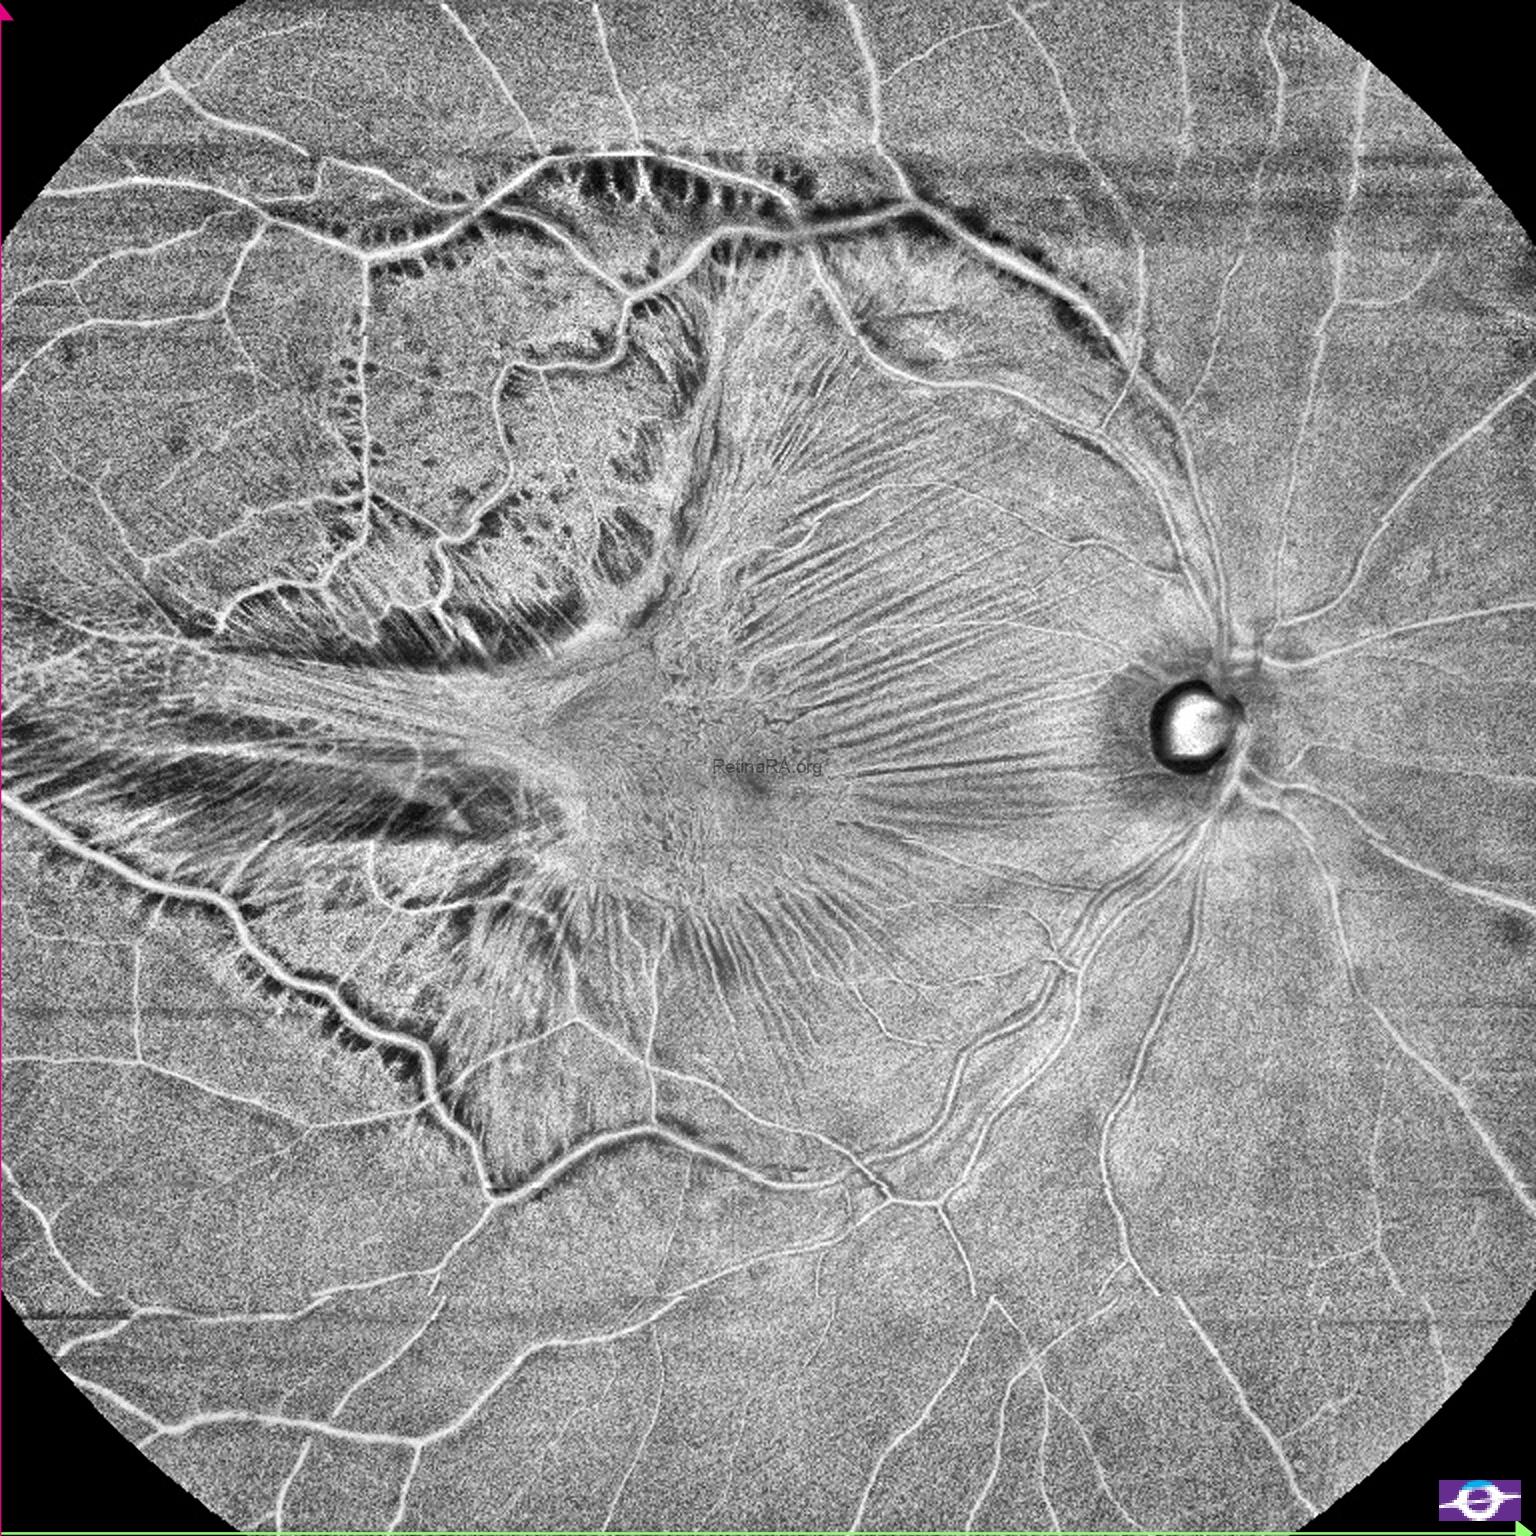

Gravitational tracks in chronic central serous chorioretinopathy: a multimodal imaging case

Patient history A 34-year-old male patient with a history of chronic central serous chorioretinopathy (CSC) [...]